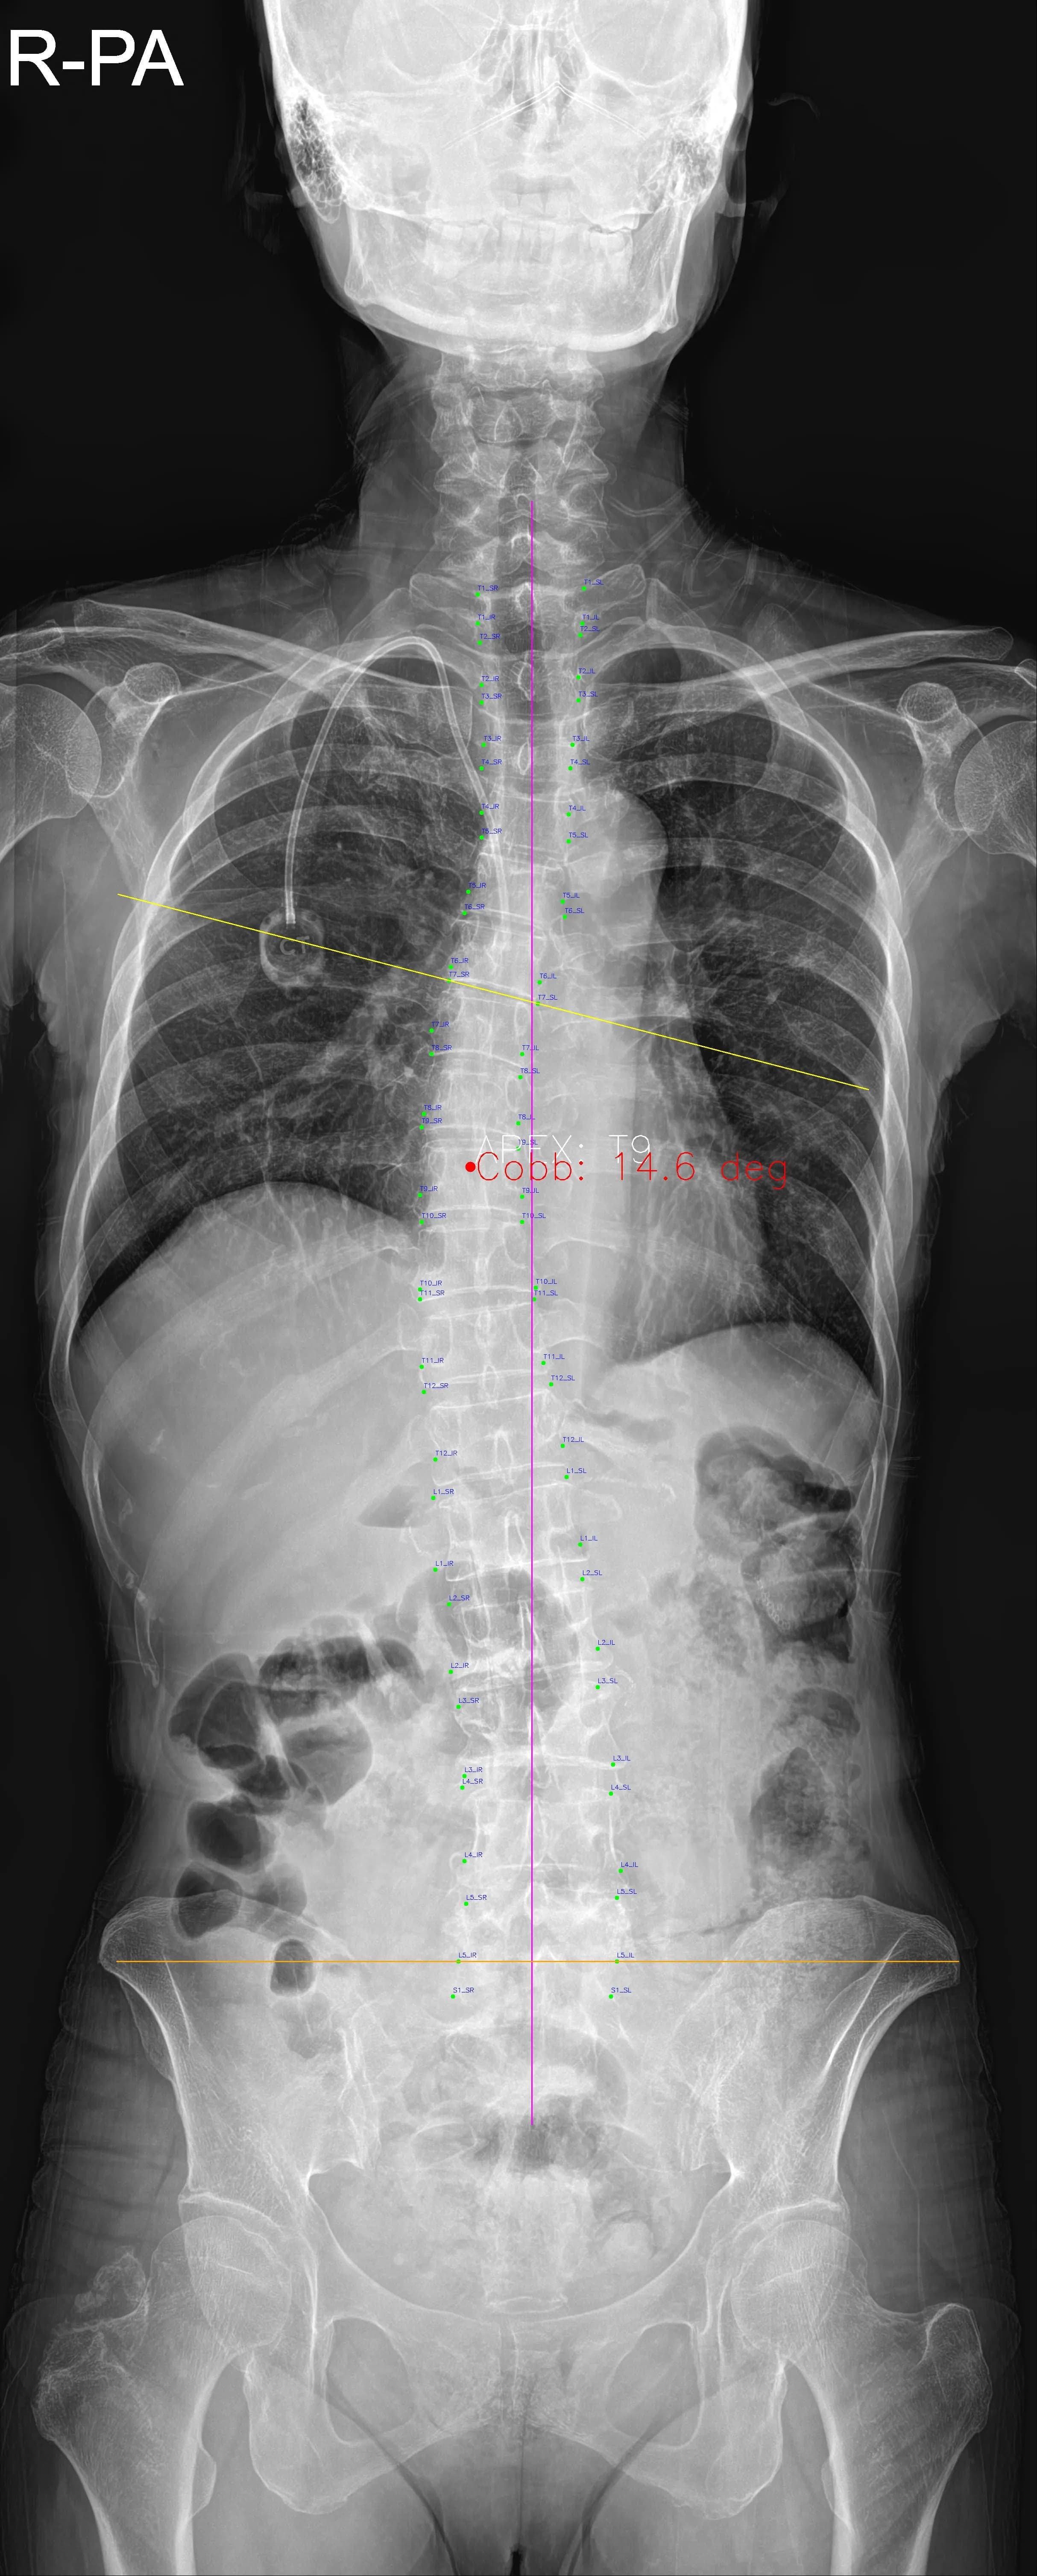

Musculoskeletal X-ray AI Analysis

부위를 클릭하여 결과 이미지를 확인하실 수 있습니다.